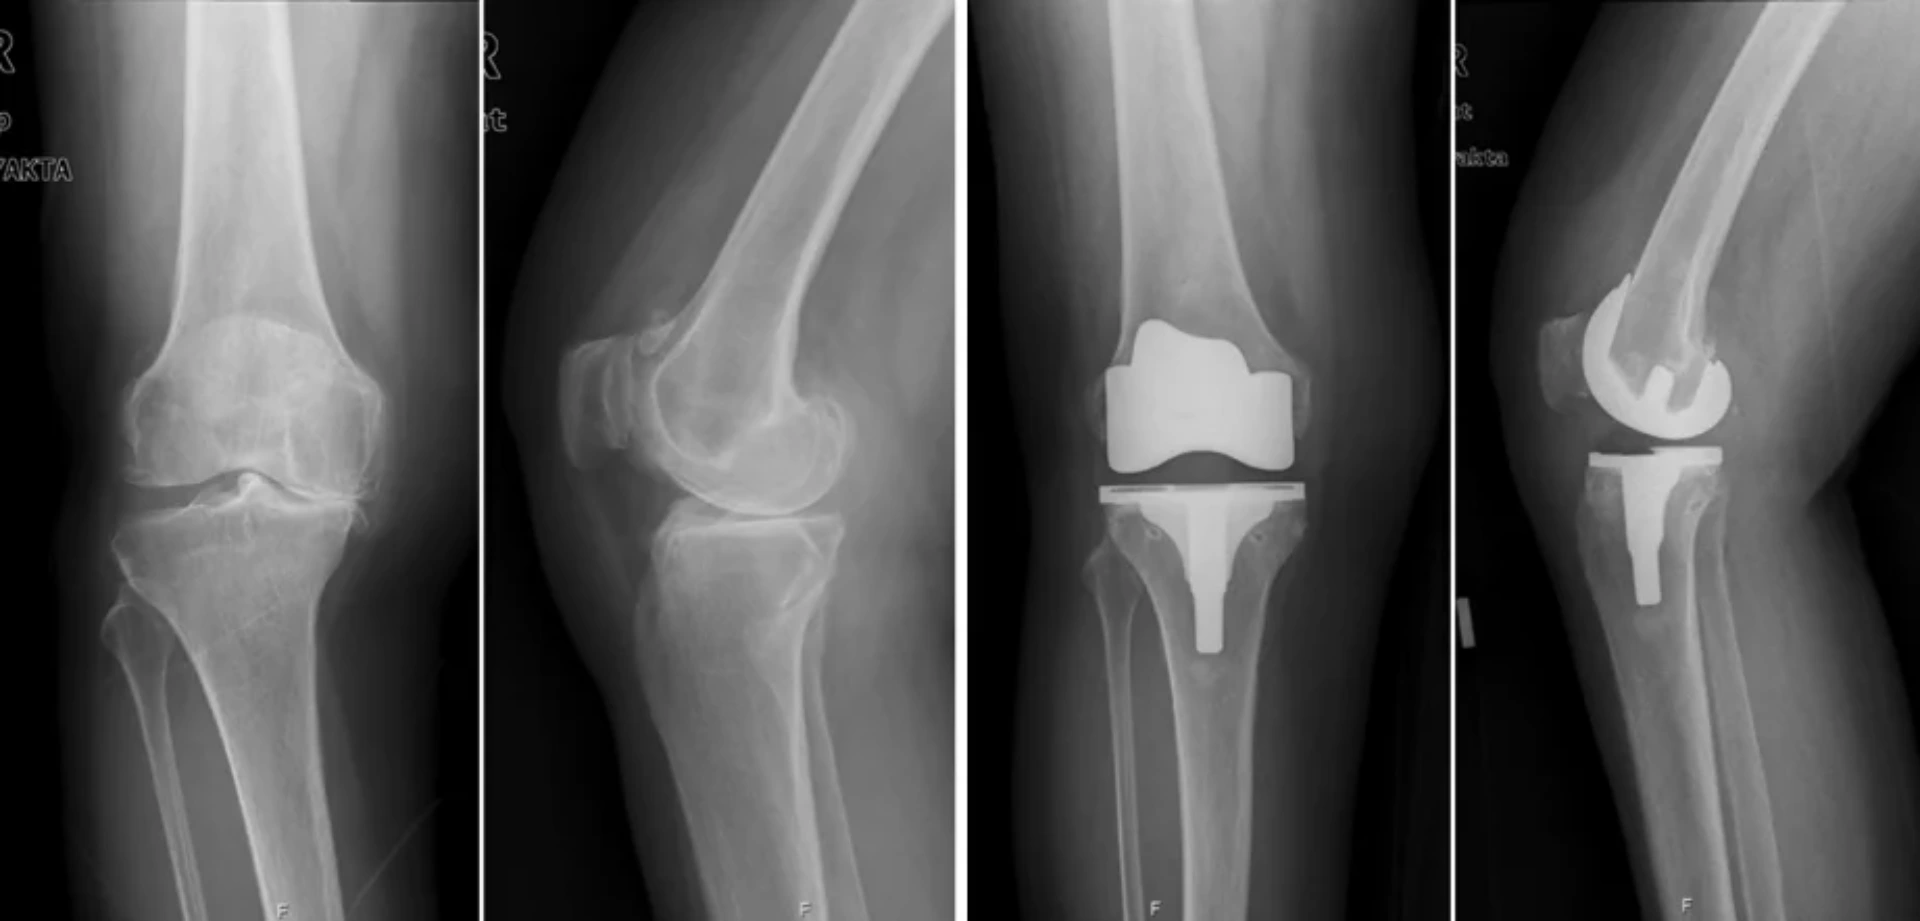

Diz artroplastiyası nədir? Diz artroplastiyası diz oynağında zədələnmiş və ya degenerativ toxumal ...